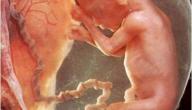

تُعَدُّ المشيمة (بالإنجليزيّة:Placenta) واحدة من أهمِّ الأشياء التي تنمو داخل الرحم خلال فترة الحمل، حيث إنّها تنمو وتكبر داخل الرحم كما الجنين، إلا أنَّها تتَّخذ شكل الفطيرة، وعادةً ما يبلغ قطرها عند الولادة حوالي 22 سم، ويصل سمكها من المنتصف إلى حوالي 2.5 سم، وتُعتبَر المشيمة نقطة التواصل بين الأم وجنينها؛ حيث ينقل دم الأم الأكسجين والعناصر الغذائيّة المهمَّة لنمو الجنين إلى المشيمة، لينقلها الحبل السرِّي من الجانب الآخر إلى الجنين، وعلى الرغم من تناقل المواد عبر الدم بين الأم وجنينها من خلال المشيمة أثناء الحمل؛ إلا أنَّ دمهما لا يختلط، بل تحافظ المشيمة على دم الجنين مفصولاً عن دم الأم.[١]

يرتبط تكلُّس المشيمة بمضاعفات مُتعدِّدة تُؤثِّر في صحَّة الجنين، وتعتمد هذه المضاعفات على الوقت من الحمل، وشِدَّة التكلُّس، فقد يرتبط تكلُّس المشيمة المُبكِّر بانخفاض وزن الطفل عند الولادة،[١] ومن ناحية أخرى، وانطلاقاً من فكرة أنَّ تكلُّس المشيمة ما هو إلا حالة من تجمُّع رواسب الكالسيوم داخل المشيمة، فإنَّ هذه الرواسب تُعيق نقل الأكسجين والغذاء إلى الجنين، ممَّا يُعَدُّ حالة خطيرة تُؤدِّي إلى حدوث ولادة مُبكِّرة، وفي الجانب الآخر قد يُؤدِّي نقص الأكسجين إلى تلف دماغ الجنين، ويكون قاتلًا.[٢]